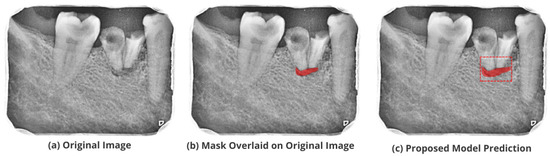

3.5. Comparison with Test Images

The proposed model accurately predicts and localizes the lesions as depicted in Figure 10, Figure 11, Figure 12, Figure 13 and Figure 14. The results indicate that the model makes predictions similar to that of the annotated masks using the periapical radiographic images. Additionally, the proposed model was evaluated based on performance indicators like precision, recall, F1 score, and accuracy for each classified periodontal lesion. The obtained results indicate that the proposed backbone network provides good performance for disease classification. All the test images for the proposed study show a 95% confidence level indicating that the database annotations are in the right direction.

Figure 13.

Test performance for the localization of a ’Primary Periodontal’ lesion.